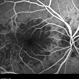

- Imaging device

-

Fundus camera

Optos Fundus Camera - Description

- 65-year-old-male with curtain/veil over vision for two days.